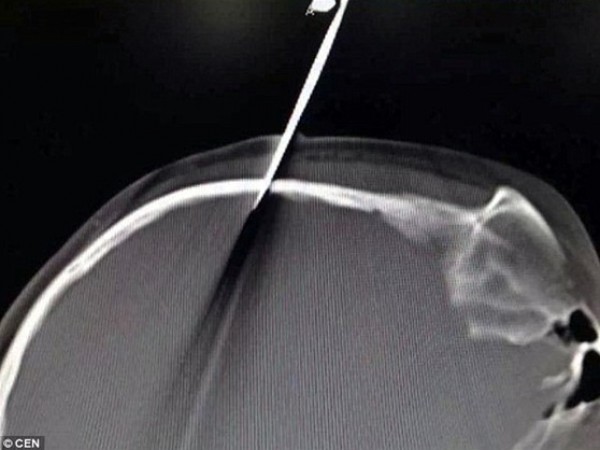

أصيبت طفلة تبلغ من العمر 10 سنوات باختراق في الجمجمة من طرفى مقص حاد بعد أن ألقاه والدها نحوها في محاولة منه لتأديبها.

وفقا لما نشرته صحيفة "ديلى ميل" البريطانية، وقع الحادث بمدينة شنجهاى عندما ألقى الأب المقص نحو إبنته ليستقر بجمجمتها عن طريق الخطأ، أثناء محاولته تخويفها بينما تلعب أثناء أداء واجباتها، لكن الطفلة لا تتذكر ما حدث.

نقلت الطفلة بشكل سريع إلى المستشفى لإزالة المقص البالغ طوله 6 بوصات من راسها، وأكد الأطباء بعد غزالته أنه لحسن الحظ لم يخترق الأوعية الدموية الرئيسية بالرأس.